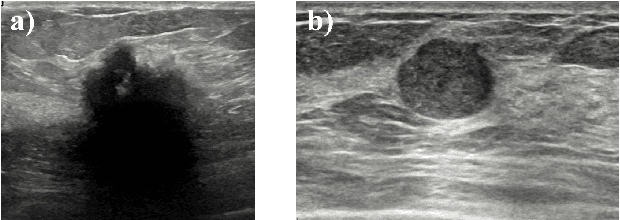

Abstract:Standard classification methods based on handcrafted morphological and texture features have achieved good performance in breast mass differentiation in ultrasound (US). In comparison to deep neural networks, commonly perceived as "black-box" models, classical techniques are based on features that have well-understood medical and physical interpretation. However, classifiers based on morphological features commonly underperform in the presence of the shadowing artifact and ill-defined mass borders, while texture based classifiers may fail when the US image is too noisy. Therefore, in practice it would be beneficial to select the classification method based on the appearance of the particular US image. In this work, we develop a deep meta-network that can automatically process input breast mass US images and recommend whether to apply the shape or texture based classifier for the breast mass differentiation. Our preliminary results demonstrate that meta-learning techniques can be used to improve the performance of the standard classifiers based on handcrafted features. With the proposed meta-learning based approach, we achieved the area under the receiver operating characteristic curve of 0.95 and accuracy of 0.91.

Abstract:We propose a novel deep learning based approach to breast mass segmentation in ultrasound (US) imaging. In comparison to commonly applied segmentation methods, which use US images, our approach is based on quantitative entropy parametric maps. To segment the breast masses we utilized an attention gated U-Net convolutional neural network. US images and entropy maps were generated based on raw US signals collected from 269 breast masses. The segmentation networks were developed separately using US image and entropy maps, and evaluated on a test set of 81 breast masses. The attention U-Net trained based on entropy maps achieved average Dice score of 0.60 (median 0.71), while for the model trained using US images we obtained average Dice score of 0.53 (median 0.59). Our work presents the feasibility of using quantitative US parametric maps for the breast mass segmentation. The obtained results suggest that US parametric maps, which provide the information about local tissue scattering properties, might be more suitable for the development of breast mass segmentation methods than regular US images.